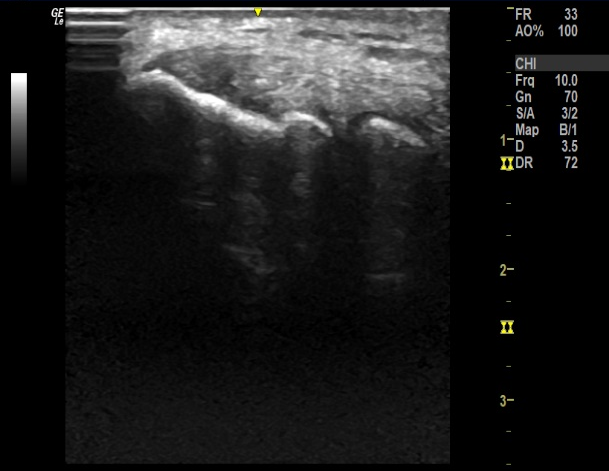

? ? ? ? 利用超聲探頭對(duì)肌肉、韌帶、神經(jīng)及關(guān)節(jié)進(jìn)行檢查,輔助診斷頸肩腰腿痛疾??;

? ? ? ? 借助超聲影像實(shí)時(shí)成像的特點(diǎn),追蹤針尖軌跡,定位病灶實(shí)施精準(zhǔn)定位注射。

? ? ? ?實(shí)時(shí)顯像,檢查過(guò)程中可實(shí)時(shí)發(fā)現(xiàn)病灶部位,無(wú)輻射,預(yù)約方便;